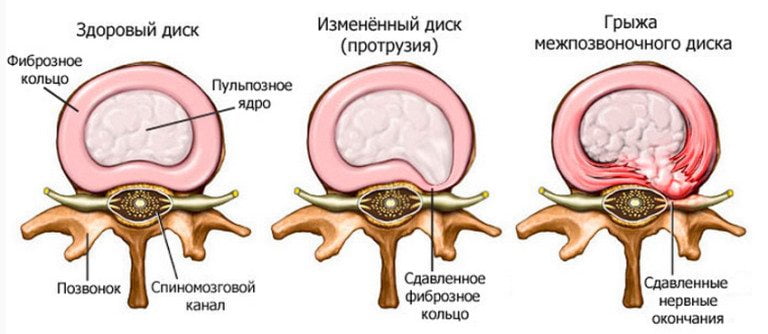

Межпозвоночная грыжа любой локализации — это часто возникающее осложнение остеохондроза. Развитие этой дегенеративно-деструктивной патологии сопровождается истончением, уплотнением межпозвонкового диска, утратой им амортизирующих свойств. При остеохондрозе 2-3 степени фиброзное кольцо расслаивается, а пульпозное ядро смещается в позвоночный канал. Нередко целостность кольца полностью нарушается с формированием опасной разорвавшейся грыжи. На фоне истончившегося диска тела соседних позвонков: